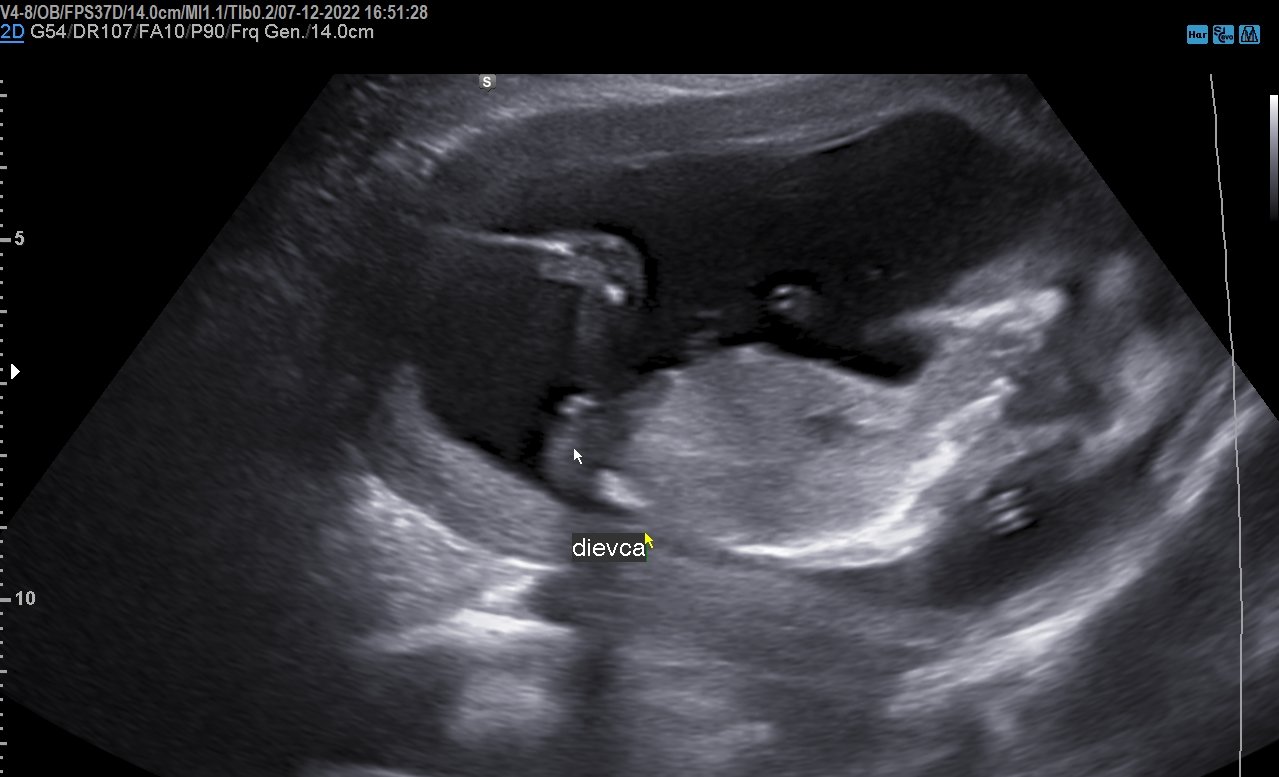

@prskavka2223 ahoj už sa bábo asi narodilo, povedala by som že to je dievčatko... či?